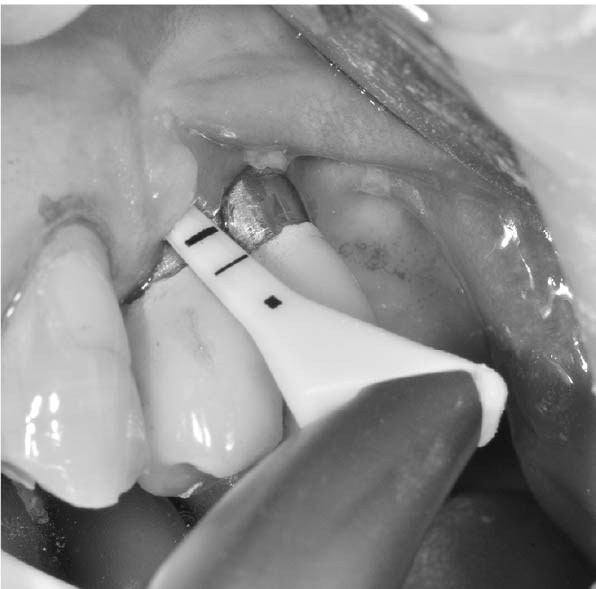

インプラントの周りを専用の器具(プローべ)で軽くなぞるように触ってみて歯茎から出血するか調べる

出血すれば炎症が起きている証拠

(1)歯ブラシの指導を行う

(2)インプラントと歯茎の隙間(歯周ポケット)を専用の器具(エアーフロー)を用いて、特殊な粉を水流で吹き付けて汚れを洗浄する

(3)歯周ポケットに抗生剤の薬を塗布